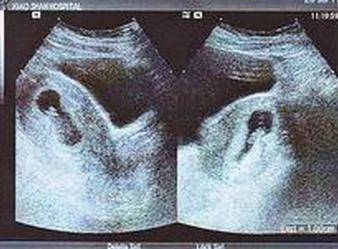

一、看孕囊分男女:拿出怀孕四十到五十天的孕妇B超单,仔细查看孕囊的形状和大小;当孕囊形状像椭圆又或者圆的时候那女孩的几率就很大,要出现长条形那男孩的几率就很大。

二、看双顶径和股骨长分男女:双顶径就是孩子的头部横直径,而股骨长就是孩子的大腿骨长度,很多人的看法,如果头大腿短那男孩的几率很大,反之头与腿相差小就是女孩。